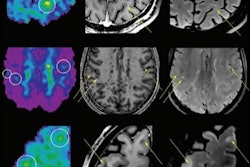

French researchers appear to have unearthed a significant discovery in the imaging of multiple sclerosis patients. They have found that lesions enhanced by two contrast agents -- gadolinium and ultrasmall superparamagnetic iron oxide particles -- were larger and exhibited a more aggressive evolution than lesions that were visible with only one contrast agent. Go to our MRI Digital Community, or click here.